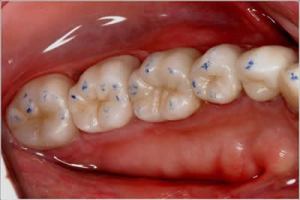

After a lot of pushing and asking a series of “why” questions, the doctor did a bite analysis and figured out something that I hadn’t known before. Two teeth were impacting really hard on the tooth with the infection. I am honestly shocked that after $2,000 worth of TMJ Bite Analysis Testing, that my previous dentist was not able to figure this out and adjust the bite three years ago, before I even had the first root canal done. All it took was a simple bite test with crayon-coated paper to figure this out (see below).

MarkLefkoDots

Crayon-like material on a piece of paper, blue on the top, red on the bottom, tells which teeth are hitting where. A basic examination that should be done with anyone whose teeth are cracking or painful. Unfortunately, I don’t think it’s stressed in dental training, because I had to really push one of the doctors to do this test.